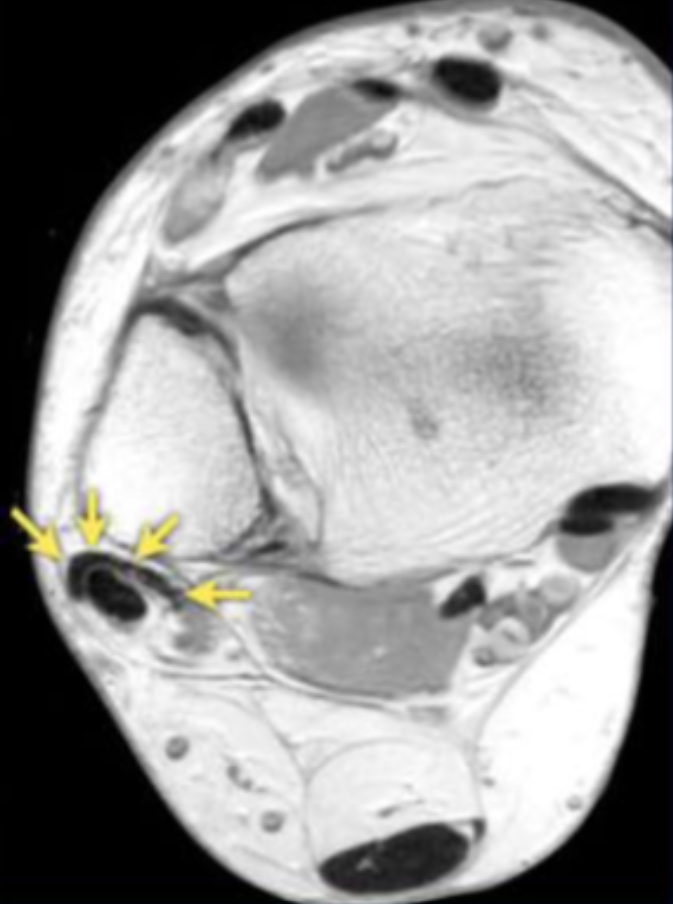

Describe the pathology indicated by the arrow (Ax PD).

Anterior talofibular ligament (ATFL) tear